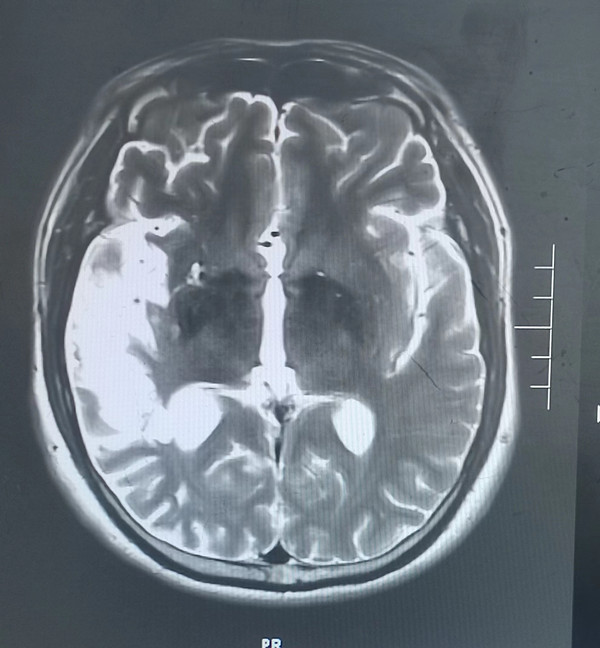

5月前46岁的徐先生因患脑梗死在西安某医院就诊,经治疗后好转,近1周再次出现脑梗死症状来我院就诊,脑梗死导致他视野缺损,左上肢肢体无力,入院后检查头颅磁共振检查发现右侧颞叶大面积脑梗死,由于错过溶栓机会,目前只能保守治疗,徐先生一家郁闷至极,平时无高血压、无糖尿病、高血脂等疾病,他按时服用药物治疗,他只是偶尔吸烟,为何反复出现脑梗死?

入院后经追问病史患者在37岁时还患有急性心肌梗死病史,当时急诊溶栓后病情好转。为明确患者反复出现脑梗死、心肌梗死原因,入院后神经内科张医生为患者做了TCD发泡试验,发现有明显异常,经食道超声检查发现患者心脏有先天性房间隔缺损。为明确患者心梗原因,我们先行冠状动脉造影并未发现有严重冠脉狭窄病变,经我院吴栋梁院长及崔旭辉主任介入团队再次评估后考虑患者属于典型的房间隔缺损出现反常栓塞病案。